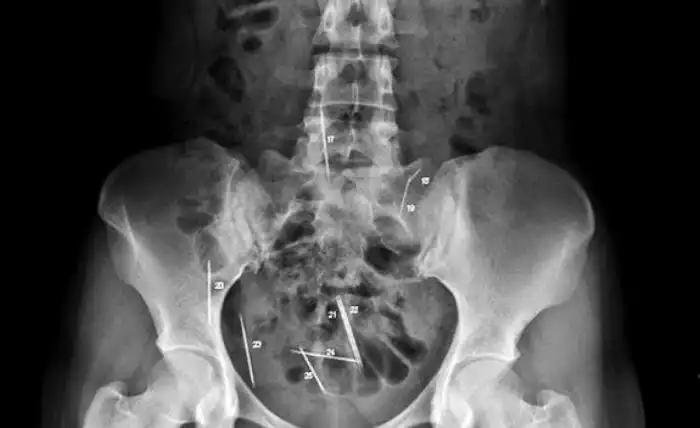

Необычные предметы в теле людей на рентгеновских снимках

На рентгеновских снимках людей порой можно обнаружить самые необычные предметы, которые находятся в их теле.